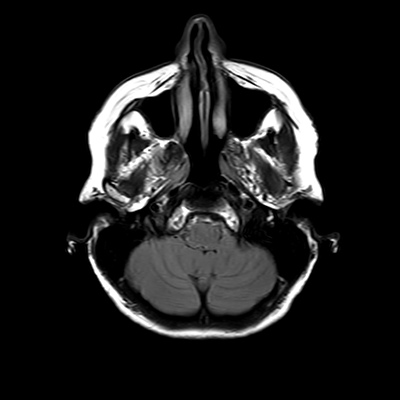

You also obtain an MRI of his brain once it's clinically safe to do so.

MRI brain (FLAIR)